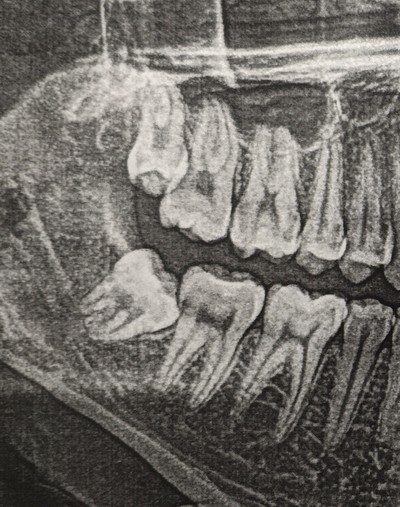

Красным пунктиром я выделил границы этой кисты на срезах компьютерной томографии. Зуб, как вы можете заметить, находится аж у угла челюсти. Если говорить простым языком, то зуб сместился ввиду давления, которое формируется внутри кисты, за счёт чего, кстати, она и увеличивается. Киста достаточно большая, в связи с чем корни 6-го и 7-го зуба были вовлечены в воспалительный процесс. Если сравнить расположение 8-ки с противоположной стороны, то можно заметить, что она располагается намного ближе к 7-му зубу.

С 6-кой все понятно. В нем когда-то были вылечены каналы (белые полоски в корнях зуба – пломбировочный материал), а вот в 7-м зубе такую манипуляцию не проводили. Необходимо убедиться, а живой ли он. В данном случае проводится специальная холодовая проба, которая позволяет понять – живой зуб или нет. Выяснилось, что 7-ка пала смертью храбрых. В таком случае каналы в этом зубе также необходимо пролечить, что и сделали наши великолепные терапевты до удаления.